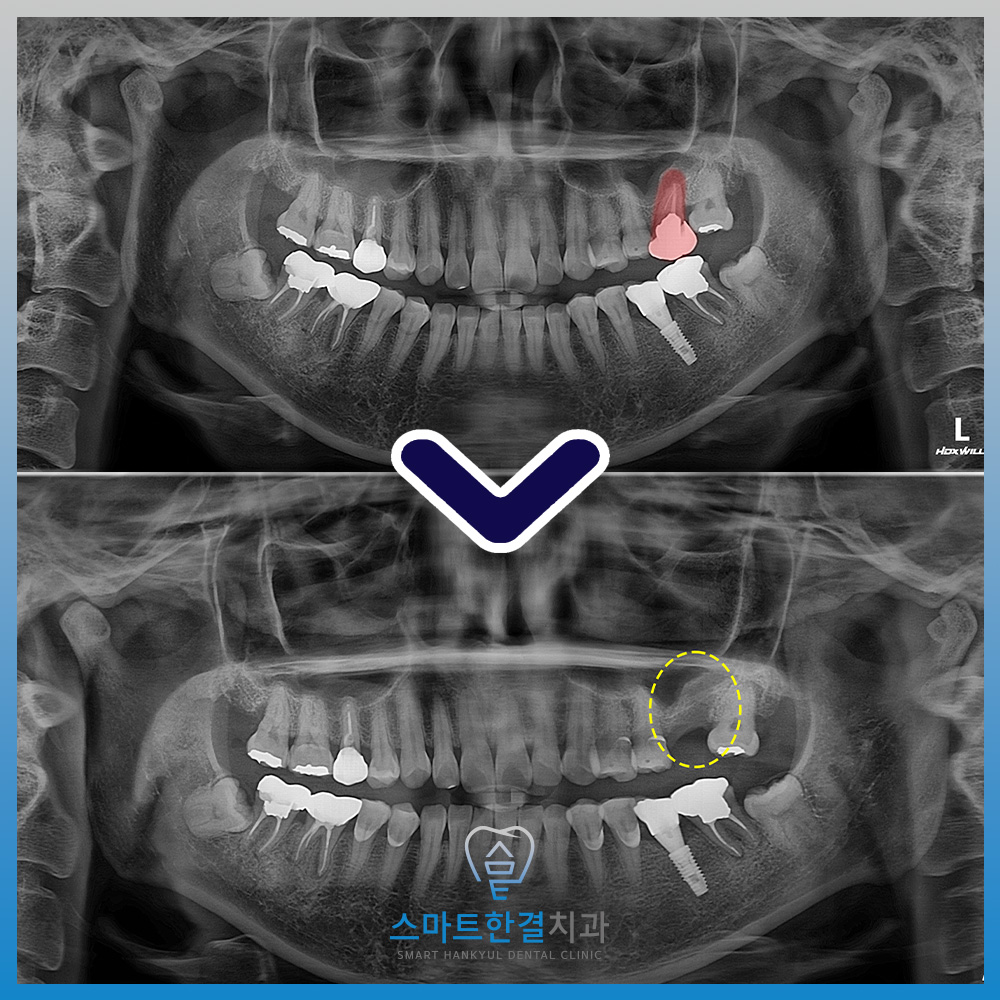

자세히 확인을 하기 위해

파노라마 촬영을 해보았는데요.

해당 치아 뿌리 끝에

염증이 크게 잡혀있는 것을

확인할 수 있었어요.

발치 후 파노라마 사진을 촬영하여

염증 부위가 남아 있지 않고

발치와 주변이 깨끗하게 정리된 것을